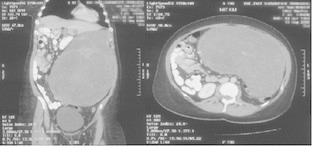

Desmoid tumours are a rare entity and are usually detected with a certain delay, as they initially often grow without causing any specific clinical symptoms. Although these tumours grow slowly and do not metastasise, their growth pattern remains aggressive and local tissue displacement or even destruction is common. Surgery remains the only potentially curative treatment option. Here we report on the findings of a 43-year old female patient with a large intra-abdominal desmoid tumour, resulting in the displacement of most intra-abdominal organs to the right of the patient's abdominal cavity. She successfully underwent surgical removal of the mass and recovered without complications.

硬纤维瘤是一种罕见的疾病,通常在一定时间后才被发现,因为它们最初生长时往往不会引起任何特定的临床症状。尽管这些肿瘤生长缓慢且不发生转移,但其生长方式仍然具有侵袭性,常见局部组织移位甚至破坏。手术仍然是唯一可能治愈的治疗选择。在此,我们报告一名43岁女性患者的病例,该患者患有巨大的腹腔内硬纤维瘤,导致腹腔内大多数器官移位至患者腹腔右侧。她成功接受了肿块切除手术,术后恢复良好,未出现并发症。